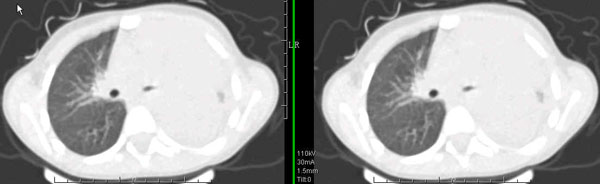

男孩,4岁,发热咳嗽4天。

下面补充ct图片:

此病人是我接手的,发热、咳嗽来做胸透,透视见左侧肺野大部密实,纵隔、心影明显左移,呼吸示纵隔摆动、膈肌矛盾运动(透视下采集了几幅图片),左肺动度明显减弱。询问病人家长,没有吃花生米等呛咳史。由于其影像特征明显,当时诊断:考虑左侧支气管异物并阻塞性肺不张、肺炎。

病人去上级医院支气管镜取出了异物。今天询问上级医院耳鼻喉科主任(是我同学),得知病人异物为胶冻样合并有少许白色粉末,后小儿说晚上喝药片时呛咳过,考虑当时为药片阻塞;另外支气管镜检发现小儿左侧支气管发育略窄,经住院抗炎治疗,现病人基本康复。

多谢各位关注及精彩点评!追踪病人结果时才知道还做过ct检查!对不起!有点晚了,刚刚下载,上传供大家参考!